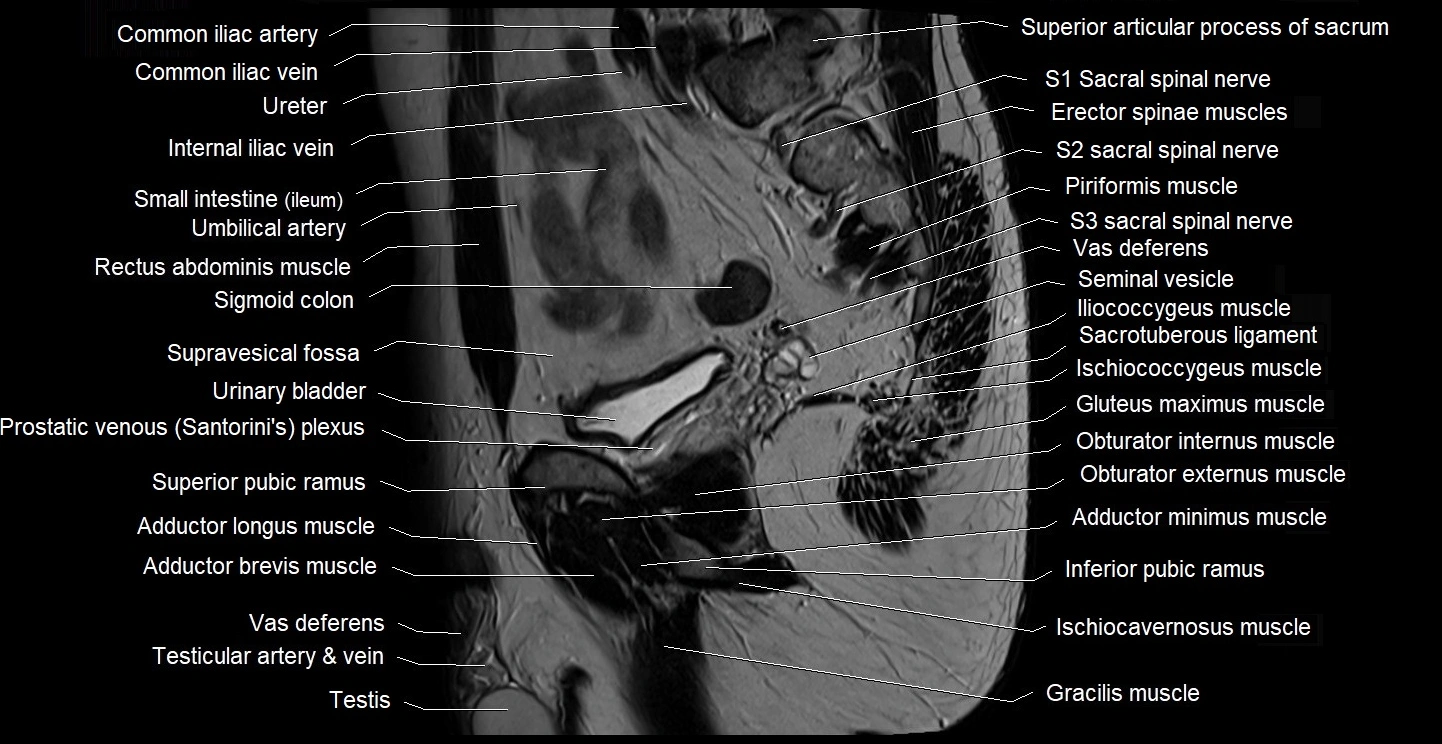

- Adductor brevis muscle

- Adductor longus muscle

- Adductor minimus muscle

- Common iliac vein

- Gluteus maximus muscle

- Gracilis muscle

- Iliococcygeus muscle

- Inferior pubic ramus

- Ischiococcygeus muscle

- Left ureter

- Lumbosacral trunk

- Obturator externus muscle

- Obturator internus muscle

- Piriformis muscle

- Psoas major muscle

- Puboprostaticus muscle

- Rectum

- Sacrotuberous ligament

- Sartorius muscle

- Seminal vesicle

- Sigmoid colon

- Superior pubic ramus

- Testis

- Vas deferens

- common iliac artery